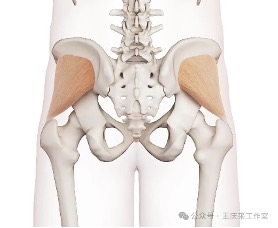

腰痛?屁股痛?你分清楚吗?

腰痛?屁股痛?你分清楚吗?腰痛?屁股痛?你分清楚吗?通常提及腰痛,大家的第一反应都是腰椎间盘突出或者腰肌劳损。但其实在腰部的附近,还有一个常常被忽视的地方——骶髂关节,它的病变往往会引起腰痛及屁股痛。临床上骶髂关节疼痛 (sacroil…51吃瓜网详情 +